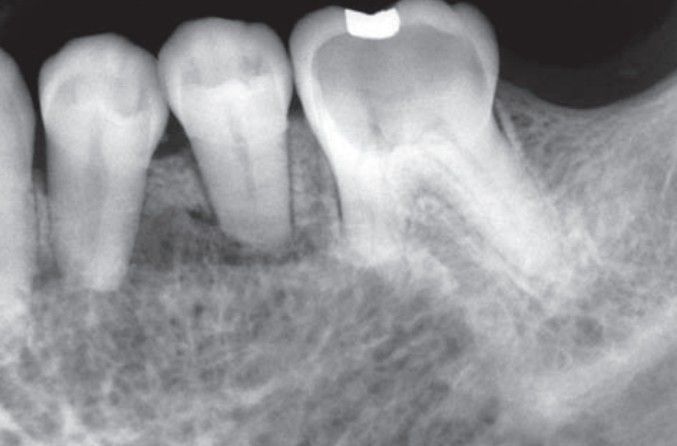

Hemangioma of alveolar bone

Hemangioma of bone showing honeycomb radiographic pattern with associated root resorption.